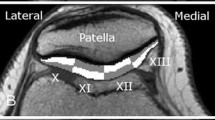

where t is n∙TE, n is the echo number, and TE is the inter-echo time. After computation of relaxation times, color-coded maps were created to allow better visual discrimination of cartilage T2 maps. Analysis was performed on three consecutive mid-sagittal slices in both femorotibial compartments. Femoral and tibial cartilages of each compartment were analyzed separately by measuring T2 distribution profiles along the articular surfaces, i.e., from an anterior to posterior direction within the cartilage. All distribution profiles were generated by manual segmentation of the femoral and tibial cartilage. Due to the relatively large voxel dimensions, the distribution of T2 relaxation times plot profiles were obtained from T2 maps by calculating the average T2 values of the all visible cartilage pixels, avoiding strict layer distribution. In order to compare the T2 profiles of different individuals (with variable articular surface lengths), the profiles were considered as functions of relative articular lengths (x), i.e., distances from a starting point and normalized to the articular length (Fig. 1). The maps were filtered in order to reduce the impact of noise and partial-volume effects of bone and synovial fluid on cartilage T2 values. Due to the image acquisition plane, we measured the femoral cartilage only in the anterior and central sub-compartments. Measurements were repeated on the same slice by the same reader at a 1-month time interval. As illustrated in Fig. 1, borders of the menisci were used to define the margins of the covered femoral and tibial cartilage. To determine regional differences of all visible cartilage, a subset analysis was performed for the medial and lateral compartment. Cartilage segmentation was performed in accordance with previous work: subdivided into sub-compartments with regard to the menisci, consistent with the regional subdivision used in Whole-Organ Magnetic Resonance Imaging Score (WORMS) [10,11,12,13]. In our study, the medial compartment was subdivided into the following sub-compartments: medial central femoral (cFM), medial posterior femoral (pFM), medial anterior tibial (aTM), medial central tibial (cTM), and medial posterior tibial (pTM). The lateral compartment was subdivided into the sub-compartments: lateral anterior femoral (aFL), lateral central femoral (cFL), lateral anterior tibial (aTL), lateral central tibial (cTL), and lateral posterior tibial (pTL) sub-compartment.

The femoral T2 distribution profiles have a more pronounced sinusoidal pattern compared to profiles seen along the tibial articular surface. The sub-compartmentation ratio was in accordance with previous studies revealing different ratios for the tibial plateaus and comparable ratios for the femoral condyles [10,11,12,13]. When adjusting the tibial plateau ratio, it was shown that the T2 distribution profiles are comparable for the medial and lateral plateau. On both sides, a similar up-sloping pattern was observed towards central and posterior sub-compartment. Conversely, the T2 distribution profiles appear to be different for the femoral condyles. The most apparent difference was observed in weight-bearing areas of the femoral condyles, with an up-sloping pattern in the lateral and a down-sloping pattern in the medial compartment. This finding is consistent with a previous study by Kaneko et al. and may be explained by the fact that the medial condyle has wider weight-bearing area than the lateral condyle, and that weight-bearing areas have lower T2 values than non-weight-bearing areas [1].

Cartilage regional variations have been demonstrated in previous studies, however cartilage distribution profiling has been described in only one [1, 30]. Two important views need to be considered in interpretation of cartilage regional variations observed with cartilage quantitative imaging. Firstly, the arrangement of the cartilage layer biochemical composition and extracellular matrix macroscopic architecture organization are unevenly distributed along the articular surfaces between compartments and sub-compartments [1, 7]. The second is the importance of the magic angle effect in T2 cartilage representation [1, 30]. The effect of angular orientation and cartilage layer on T2 values has already been established for the femoral condyles, and the observed sinusoidal pattern in femoral cartilage may be attributed to this [1]. The anatomical curvature of the femoral condyles is an important factor, however, the magic angle effect also appears to be important for the relatively flat tibial cartilage [30]. With qualitative T2 assessment, it has been shown that T2 values are higher towards the joint periphery as organization of the extracellular matrix appears to differ between the periphery and the center of the tibial plateau [30]. In our study, we observed higher T2 values towards the posterior tibial sub-compartments, however not the anterior tibial sub-compartments. To minimize the magic angle effect in our analysis, full-thickness cartilage was analyzed.